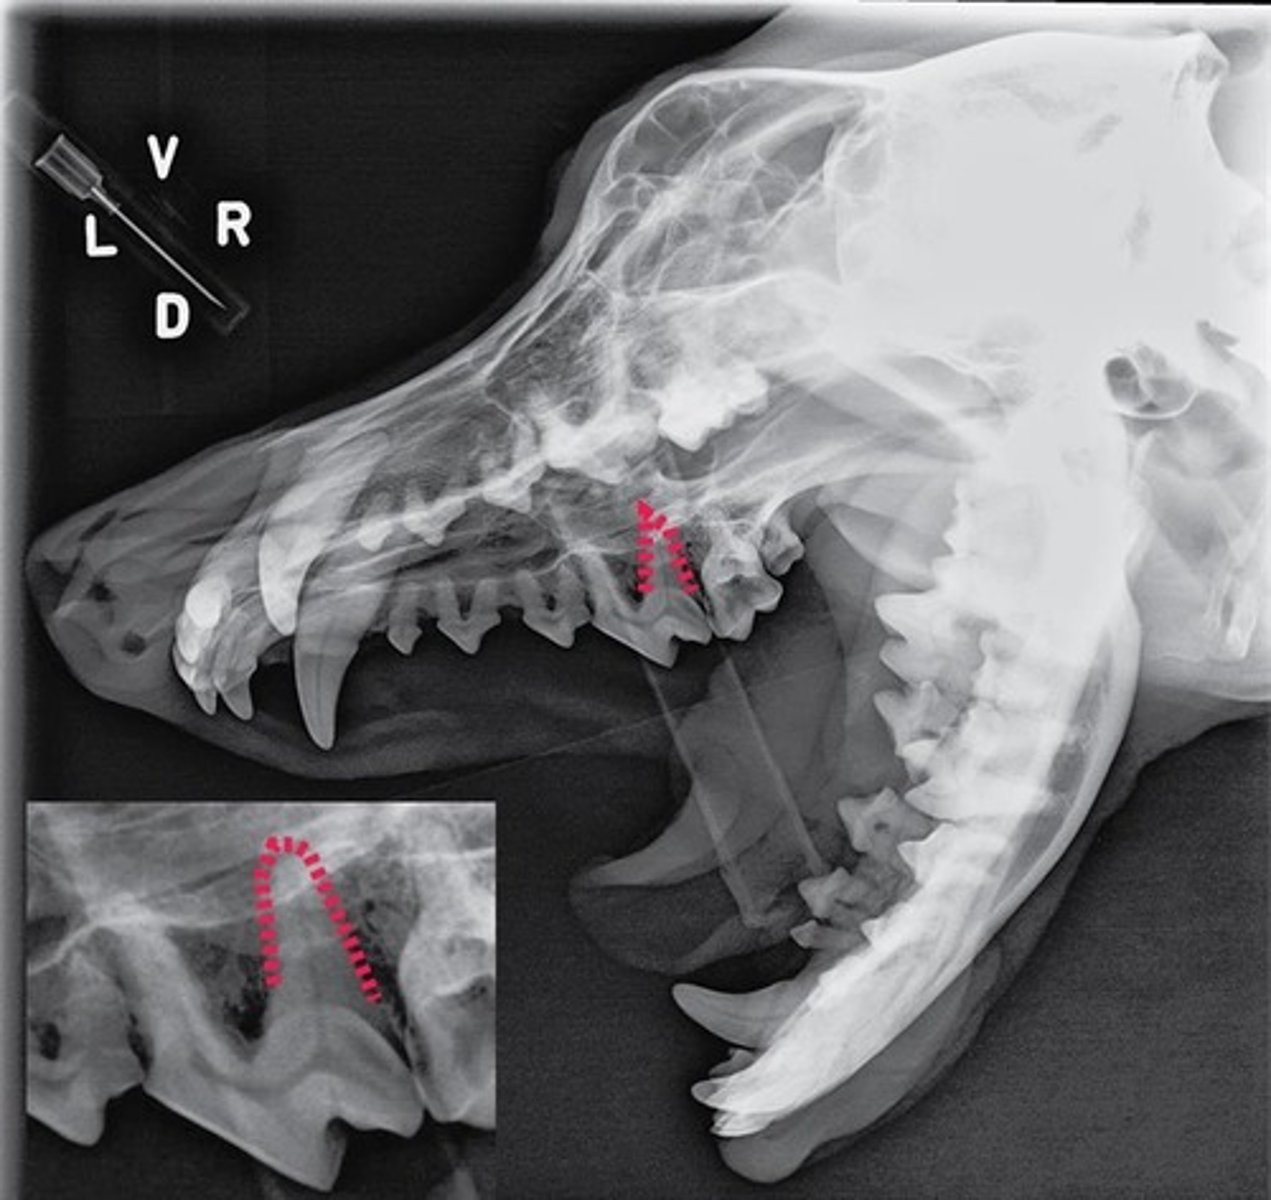

Using the Triadan system, enter the three-digit number that corresponds to the tooth pointed at by the arrow.

309

Using the Triadan system, enter the three-digit number that corresponds to the tooth pointed at by the arrow.

404

Using the Triadan system, enter the three-digit number that corresponds to the tooth highlighted.

704

Canine is #04 and in quadrant 3, so add 4 to the quadrant to get 7 and that equals 704

Triadan number for lower left deciduous canine.

premolars

molars

multiple roots

What type of teeth are the most difficult to extract?

Why?